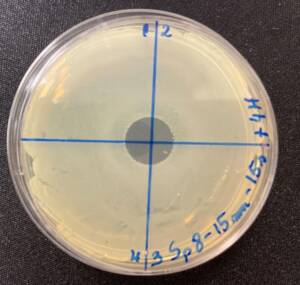

Photos of the Petri plates, 72 hours after bacterial (Pseudomonas aeruginosa) inoculation.

Image (A) shows positive bacterial growth inhibition (full translucency) at the treatment site after one dose of

UV-C for 15 seconds at 10 mm distance.

Image (B) is the control plate. The blue lines divide the plate into quadrants.